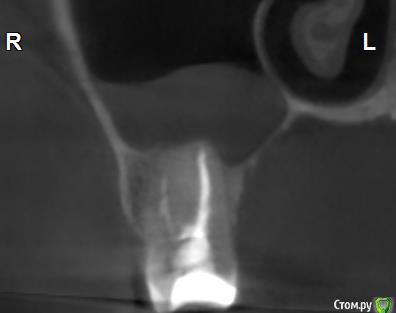

Здравствуйте! Верхний правый шестой зуб пломбировали 3 месяца назад. Примерно месяц назад он начал ныть, после насморка, сначала периодами, а теперь почти постоянно. При постукивание (ощущается не совсем так, как другие зубы) и пальпации десны он не болит. 2,5 месяца назад удаляли кисту из гайморовой пазухи. Может ли быть это какое-то воспаление и есть ли вероятность устранить его какими-нибудь антибиотиками, если да, то как, или может удалить зуб? Если есть воспаление, то какие могут быть последствия если не удалить зуб?

(Снимки с КТ, первые 8(Image) - сделаны сейчас,по 4 в разных проекциях, вторые 8(Before) - сделаны 5 месяцев назад до удаление кисты и повторного пломбирование зуба( до повторного пломбирование он реагировал на горячее, был запломбирован 3 года))

переличили зуб адекватно, во всяком случае по снимкам